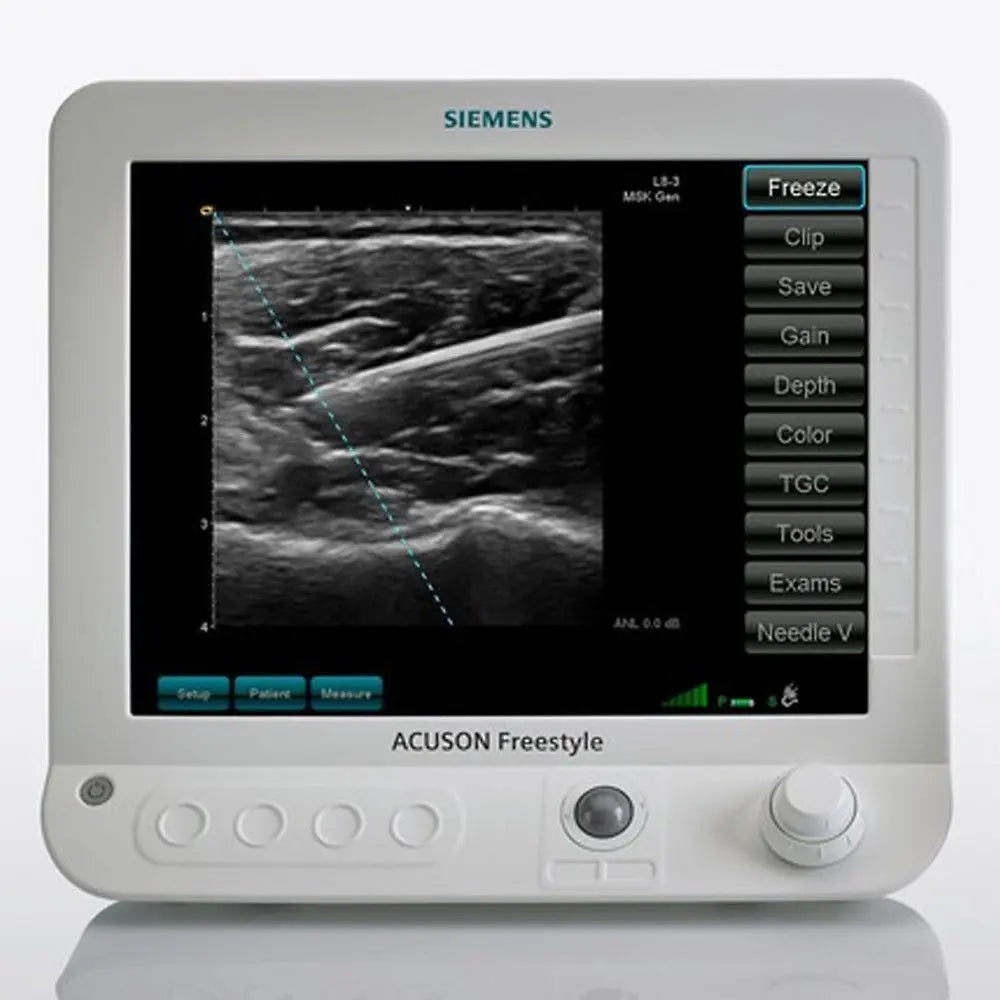

Brand: WIRELESS DEVICE

MPN: X838FRSTYLE-SCANNER-FREE-STYLE-BATTERY-CHARGE-DEVI